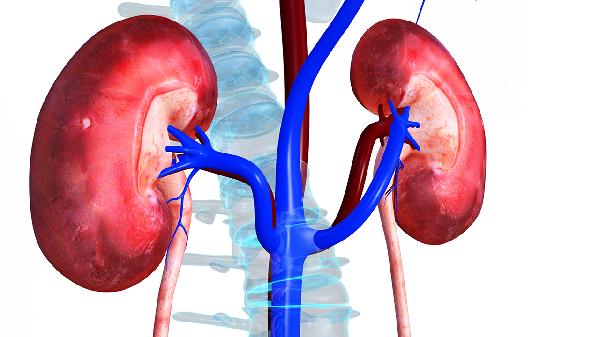

肾结石排出预兆和感觉

#肾结石#